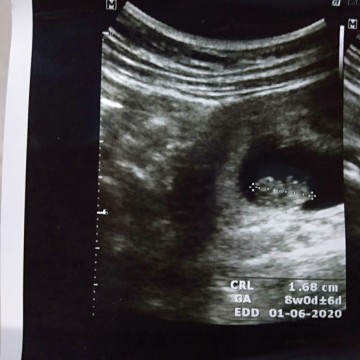

Kalau ini umur 8week bun